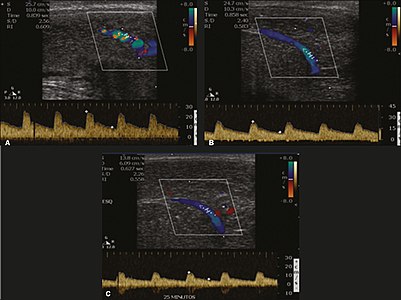

Penile ultrasonography with doppler can be used to examine the erect penis. Most cases of ED of organic causes are related to changes in blood flow in the corpora cavernosa, represented by occlusive artery disease (in which less blood is allowed to enter the penis), most often of atherosclerotic origin, or due to failure of the veno-occlusive mechanism (in which too much blood circulates back out of the penis). Before the Doppler sonogram, the penis should be examined in B mode, in order to identify possible tumors, fibrotic plaques, calcifications, or hematomas, and to evaluate the appearance of the cavernous arteries, which can be tortuous or atheromatous.[39]

Erection can be induced by injecting 10–20 µg of prostaglandin E1, with evaluations of the arterial flow every five minutes for 25–30 min (see image). The use of prostaglandin E1 is contraindicated in patients with predisposition to priapism (e.g., those with sickle cell anemia), anatomical deformity of the penis, or penile implants. Phentolamine (2 mg) is often added. Visual and tactile stimulation produces better results. Some authors recommend the use of sildenafil by mouth to replace the injectable drugs in cases of contraindications, although the efficacy of such medication is controversial.[39]

Before the injection of the chosen drug, the flow pattern is monophasic, with low systolic velocities and an absence of diastolic flow. After injection, systolic and diastolic peak velocities should increase, decreasing progressively with vein occlusion and becoming negative when the penis becomes rigid (see image below). The reference values vary across studies, ranging from > 25 cm/s to > 35 cm/s. Values above 35 cm/s indicate the absence of arterial disease, values below 25 cm/s indicate arterial insufficiency, and values of 25–35 cm/s are indeterminate because they are less specific (see image below). The data obtained should be correlated with the degree of erection observed. If the peak systolic velocities are normal, the final diastolic velocities should be evaluated, those above 5 cm/s being associated with venogenic ED.[39]